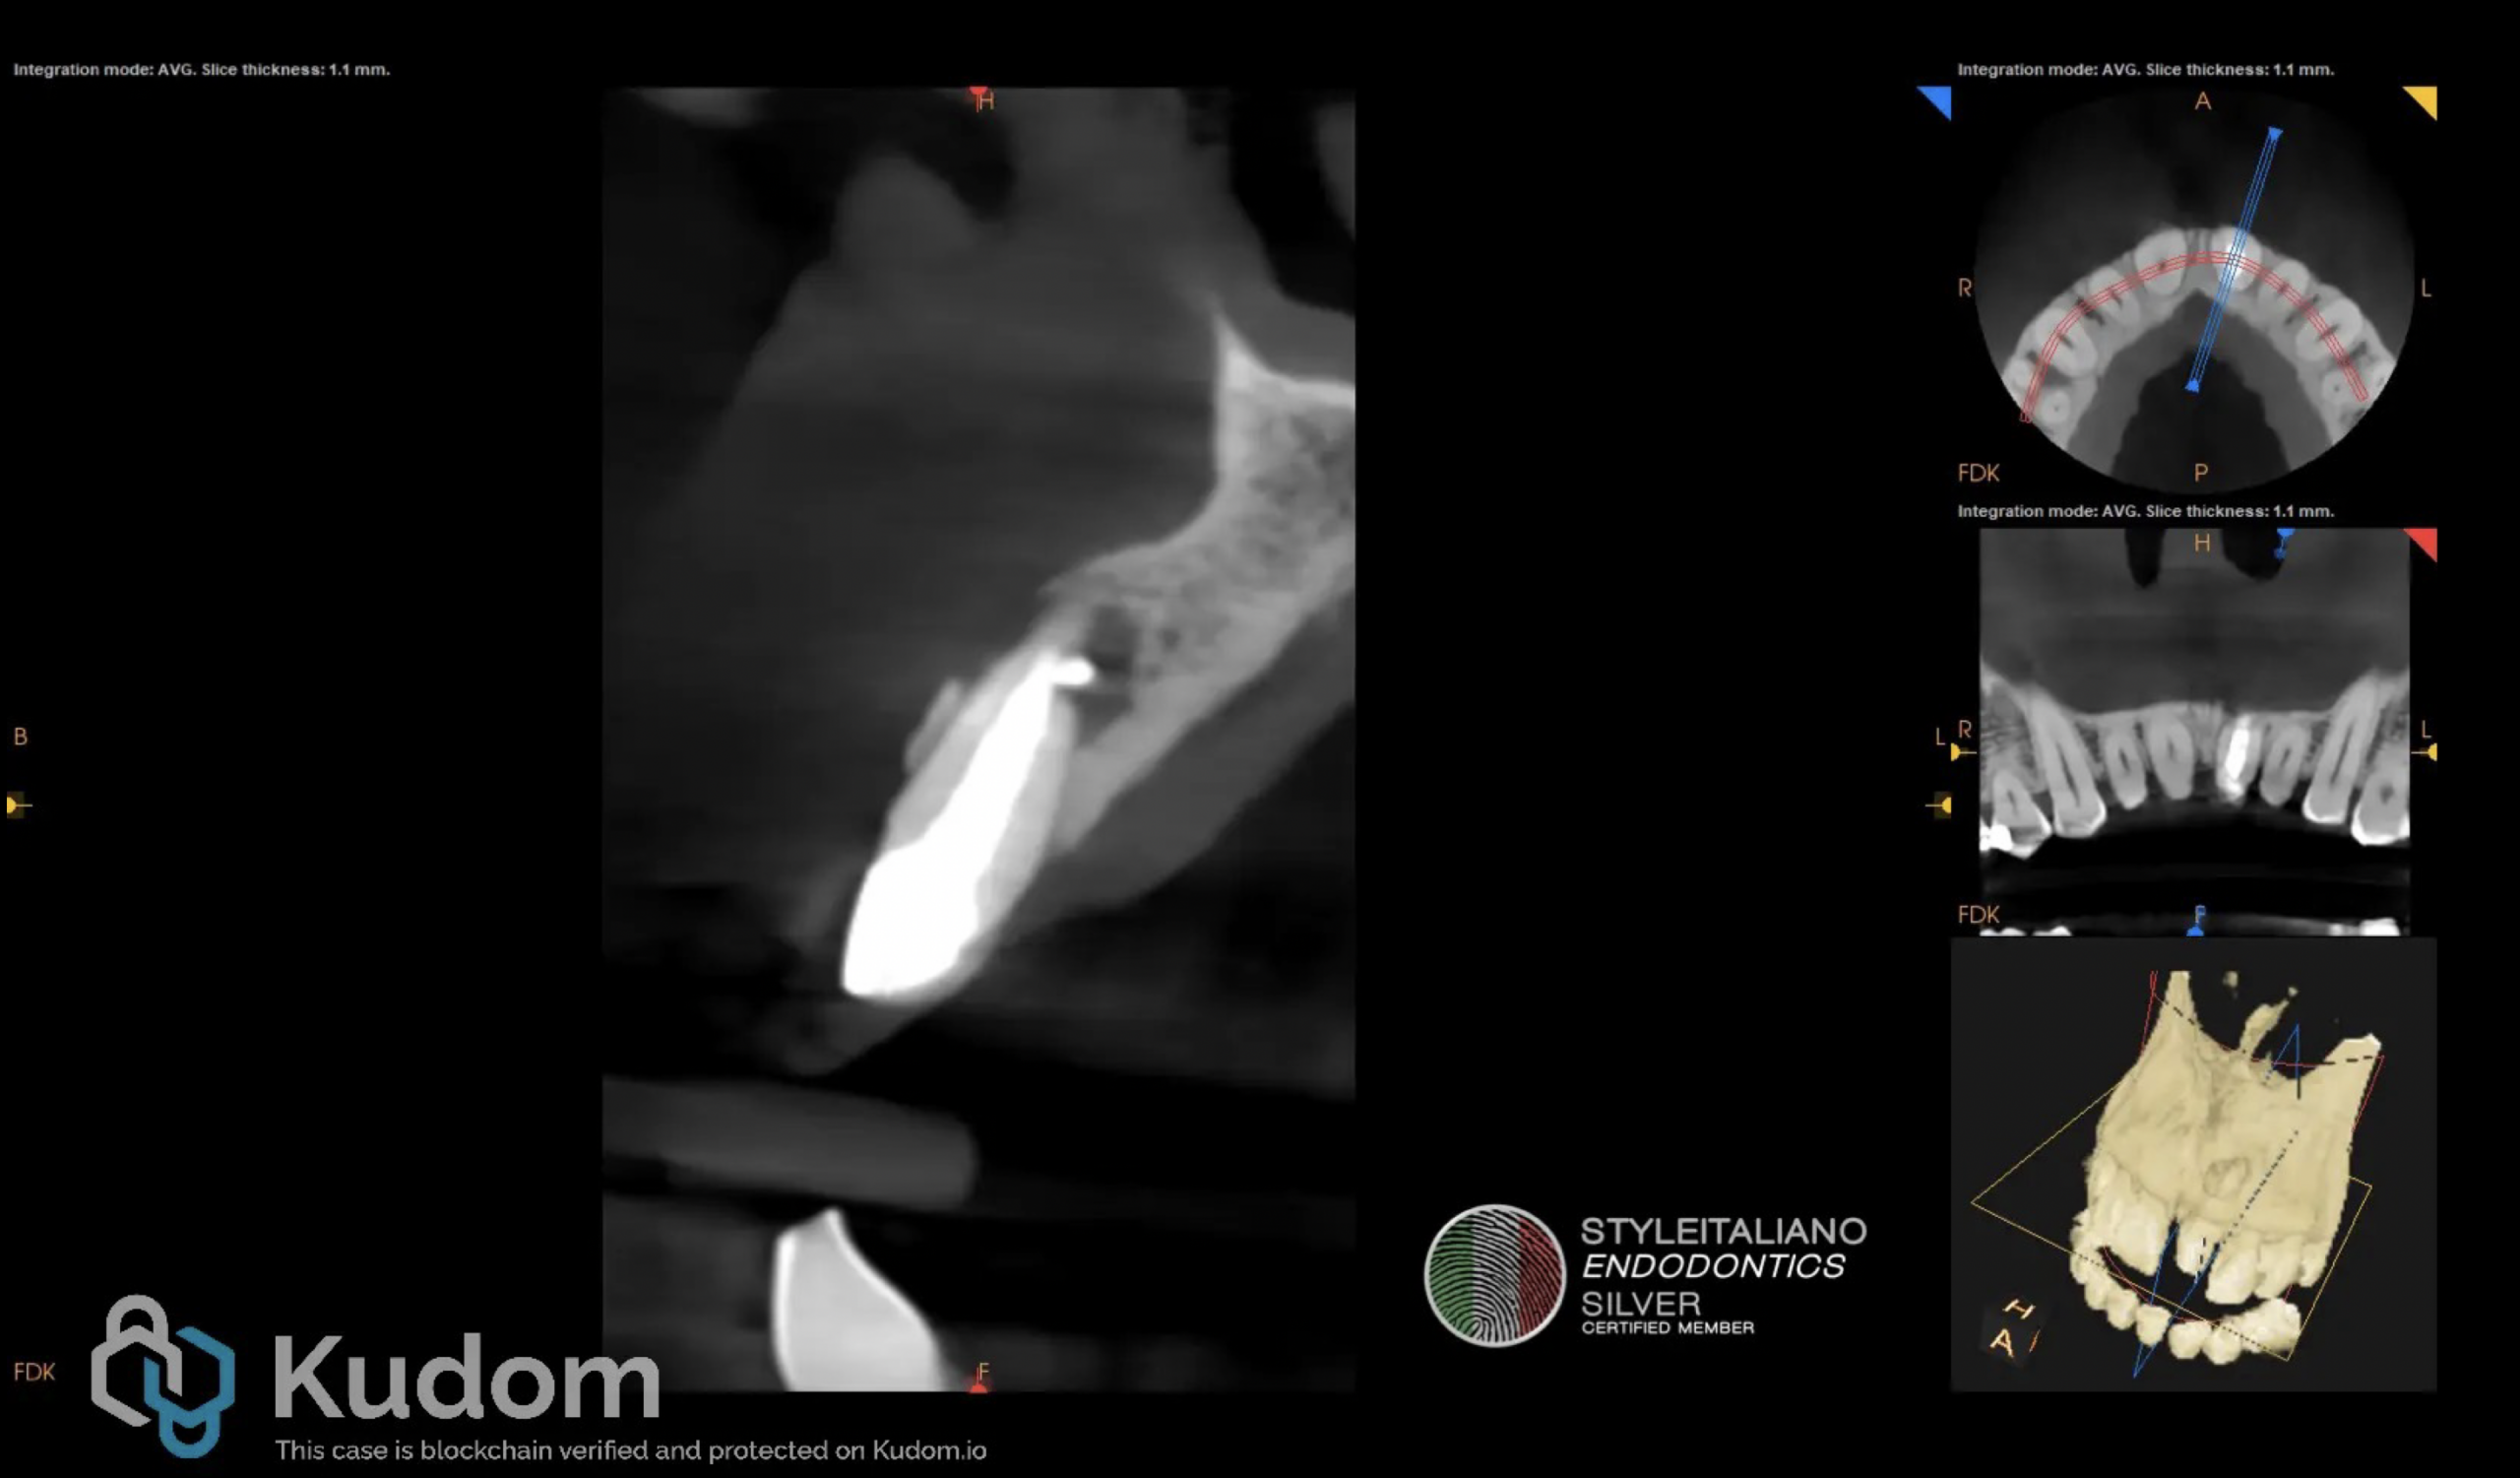

Fig. 1

A 45-year-old male patient was referred to our office for an evaluation of the upper left central incisor after the referring colleague detected an unusual canal anatomy on a periapical radiograph. The patient reported little to no discomfort and an intermittent discharge of pus through a sinus tract. After carefull clinical and radiological examination the maxillary left central incisor was diagnosed with previous root canal therapy and chronic apical abscess. The computed tomography ( CB-CT) examination revealed a well-defined radiolucency in the apical third of tooth 2.1, compatible with inflammatory root resorption as seen in Figure 1.